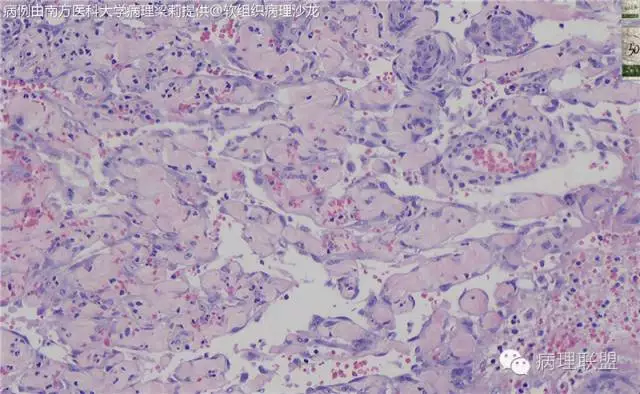

血管裂隙样,弯曲排列,似迷宫样,良性应该打不住,需往中间型考虑,请大咖们指点,软组织的重点应该放在良恶性的鉴别吧。

这例我们发的是卡波西样血管内皮细胞瘤,考虑如下:(1)新生儿,肢体肿物;(2)位置深,侵及皮下脂肪;(3)大多是裂隙状血管,也有少量吻合的血管网,细胞有异形,可见坏死

Kaposi型血管内皮瘤常有隐约小叶结构,梭形细胞束间有毛细血管,细胞核异型性和分裂活性一般不明显,常见梭形细胞束和圆形"肾小球样"实性细胞巢混合存在。

有些区域类似Kaposi肉瘤,如下图

而复合性血管内皮瘤则是由良性、中间性和恶性的成份组成,也是浸润性生长,常常侵犯皮下脂肪组织,此例细胞形态由梭形细胞、卵圆形细胞及上皮样细胞组成,形态可见良性区域、中间性区域及高分化血管肉瘤或上皮样血管肉瘤区域,因此,似乎复合性血管内皮瘤更妥。此类肿瘤可以发生于婴幼儿。当然与Kaposi型血管内皮瘤一样,同属中间性血管瘤,只是后者,若肿瘤体积大,可出现Kasabach-Merritt综合征。

这种形态若在老年人头面部就是血管肉瘤,而在婴幼儿就降级了。